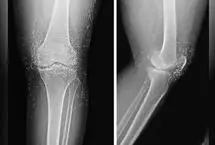

درد زانوهای این بیمار علیرغم استفاده از درمانهای دارویی مانند مسکنها، داروهای ضدالتهاب غیراستروئیدی و حتی تزریق…